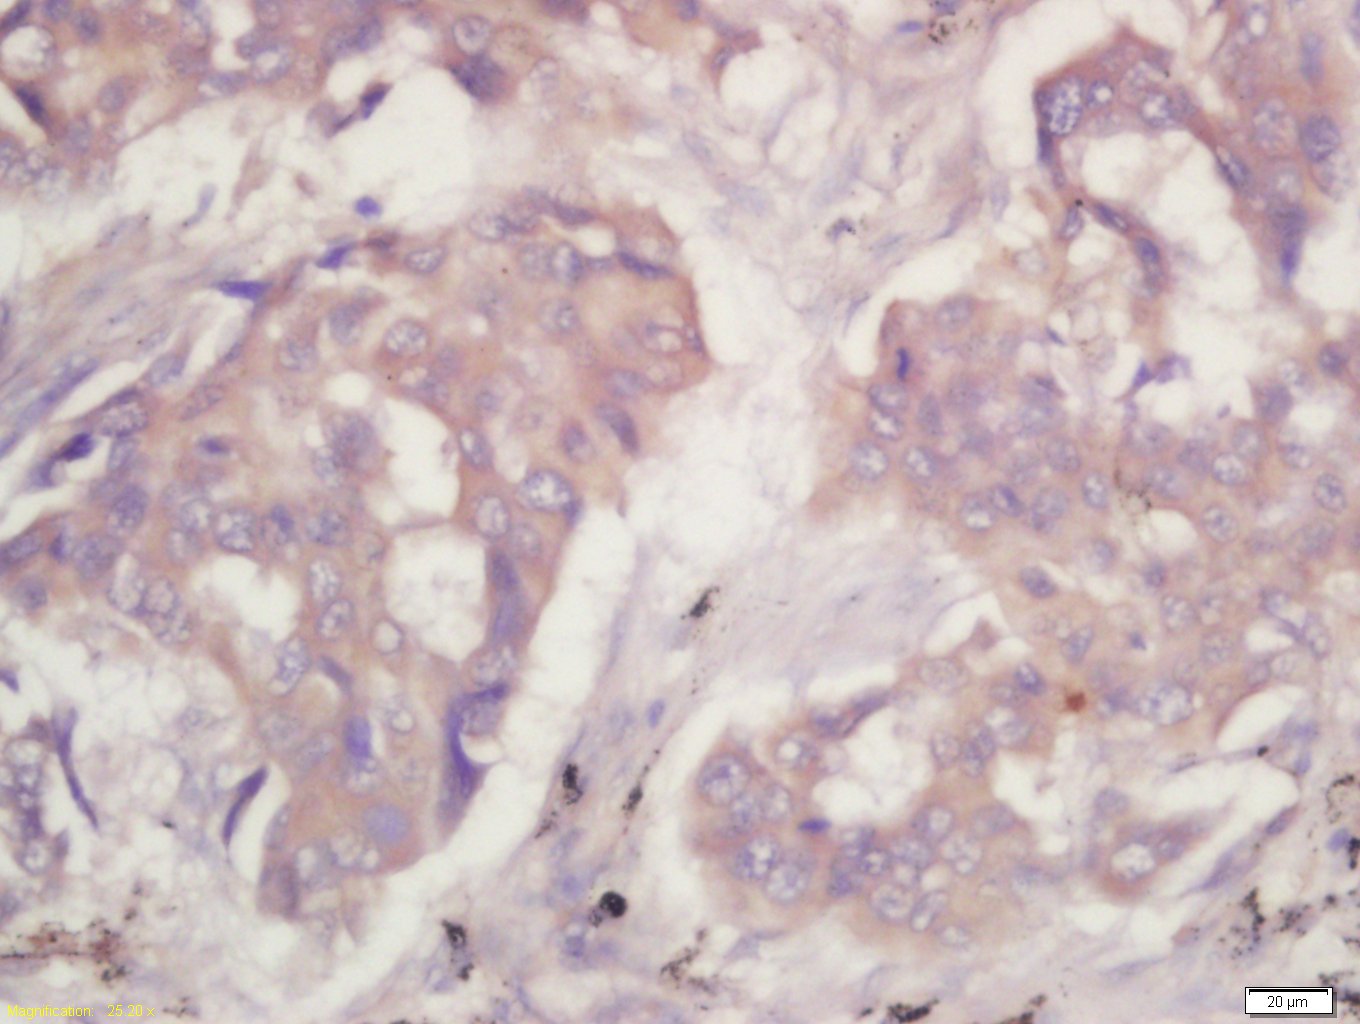

| {IHC-P} | {1:100-500} |

Antigen retrieval: citrate buffer ( 0.01M, pH 6.0 ), Boiling bathing for 15min; Block endogenous peroxidase by 3% Hydrogen peroxide for 30min; Blocking buffer (normal goat serum,C-0005) at 37℃ for 20 min;

Incubation: Anti-PKM2 Polyclonal Antibody, Unconjugated(bs-0101R) 1:200, overnight at 4°C, followed by conjugation to the secondary antibody(SP-0023) and DAB(C-0010) staining